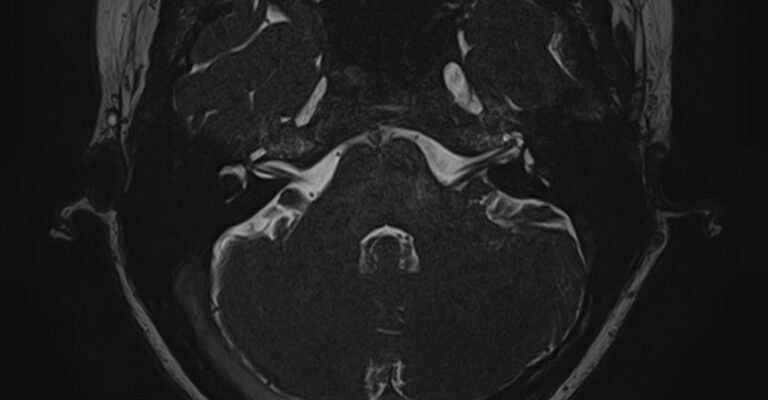

Внутреннее ухо – важная часть слуховой и вестибулярной систем тела человека, находящаяся в толще пирамиды височной кости.

Внутреннее ухо содержит слуховой орган (улитку) и орган равновесия (преддверие и полукружные каналы), патологические изменения которых в свою очередь приводят к развитию нейросенсорной тугоухости и вестибулярных нарушений.